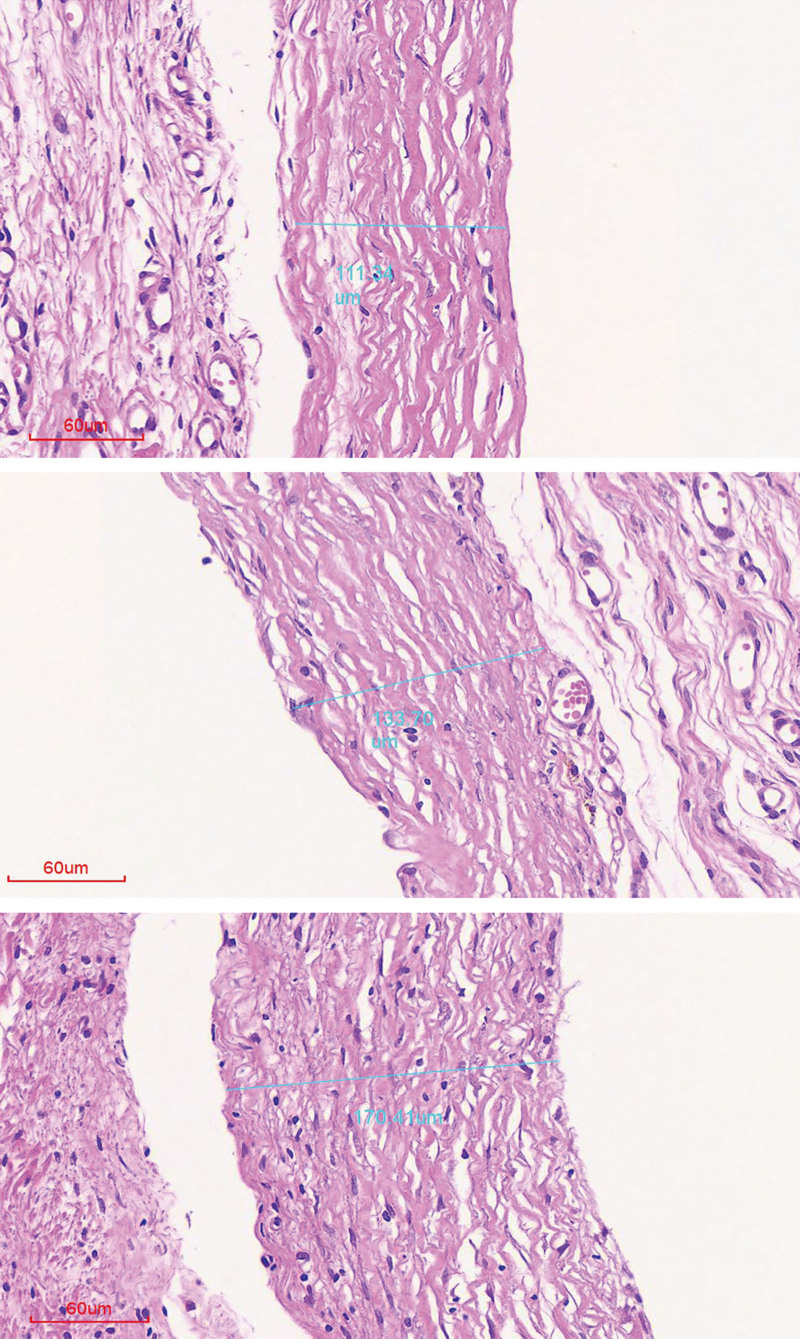

Results: Histologic analysis of the 45 capsules obtained revealed lower levels of fibrosis and acute inflammation in the group with lower hardness. This result was confirmed by immunohistochemical staining. Hematoxylin and eosin staining showed that the capsule thickness was less in the low-hardness group. In addition, inflammation resolved quickly in the low-hardness group, and mature fibrotic tissue was observed.